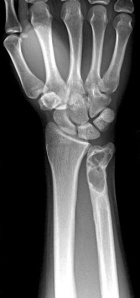

C.G. - 21 year old male with a history of curretage and bone grafting of a distal ulnar lesion eighteen months ago

Zoom image: Radiological image Radiological image.